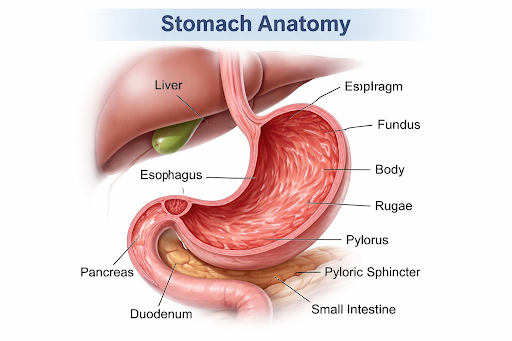

Overview of Stomach Cancer

Stomach cancer, also known as gastric cancer, is a type of cancer that develops in the inner lining of the stomach, a vital organ of the digestive system. The stomach is a muscular, hollow organ located in the upper abdomen that stores food after swallowing and helps break it down through muscular movement, stomach acid, and digestive enzymes. It plays an essential role in digestion by converting food into a semi-liquid form, protecting the body from harmful bacteria, and gradually releasing digested food into the small intestine for nutrient absorption.

Where Stomach Cancer Begins

Stomach cancer begins in the stomach, a muscular, hollow organ located in the upper abdomen between the esophagus and the small intestine. The inner lining of the stomach, which produces digestive acids and enzymes, is most commonly involved.

How Stomach Cancer Develops

Stomach cancer usually develops when healthy cells in the stomach lining undergo changes that cause them to grow uncontrollably. These altered cells may form a tumor over time. The process is often slow and may occur over several years, sometimes beginning with chronic inflammation or changes in the stomach lining.

Possible Risk Factors